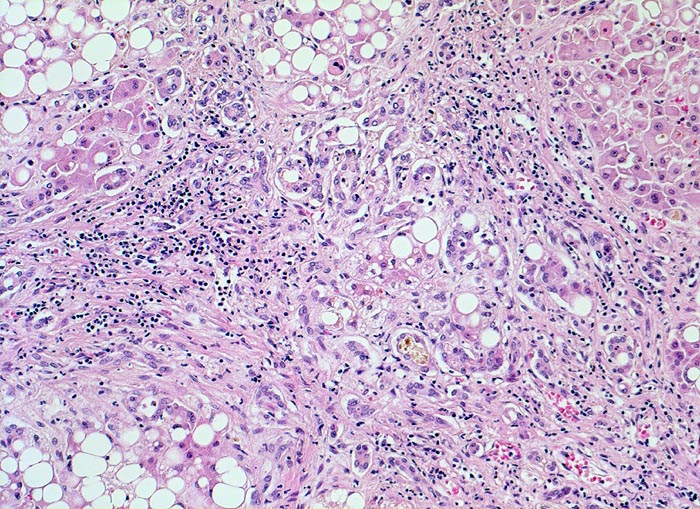

• Floride sklerosierende alkoholische Steatohepatitis: Grobtropfige Verfettung von ca. 50% des Parenchyms.Neutrophile Granulozyten umgeben einzelne Hepatozyten (Satellitose). Wenig Apoptosekörperchen. Zahlreiche Mallory Körperchen und Megamitochondrien. Perivenuläre Maschendrahtfibrose.

• Hydropische Schwellung periportaler Hepatozyten.

• Canaliculäre Cholestase in einem Zirrhoseknoten.